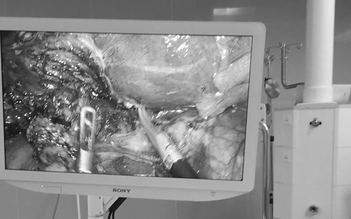

Bệnh viện đa khoa Vĩnh Long vừa phẫu thuật thành công cho một bệnh nhân bị rò túi mật - tá tràng kèm sỏi ống mật chủ. Đây là bệnh lý hiếm gặp, phức tạp và có nguy cơ biến chứng cao.